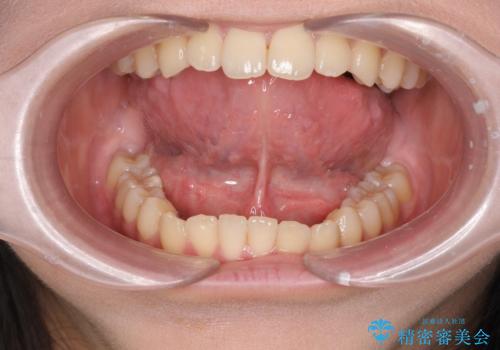

[滑舌を治したい] 舌の小帯の形成術

担当医 大元洋佑

![[滑舌を治したい] 舌の小帯の形成術の症例 治療前](https://seimitsushinbi.jp/wp/wp-content/uploads/2023/11/IMG_8451-500x350.jpg?v=1699614841)

![[滑舌を治したい] 舌の小帯の形成術の症例 治療後](https://seimitsushinbi.jp/wp/wp-content/uploads/2023/11/IMG_8901-500x350.jpg?v=1699614854)